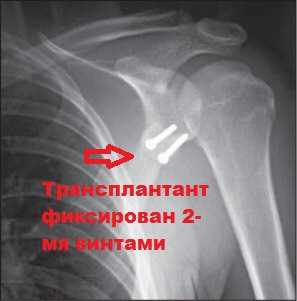

Пример реконструкции по Банкарту с фиксацией нестабильного лоскута хряща при переднем вывихе плечевого сустава

ОПЕРАЦИЯ БАНКАРТА

Для восстановления анатомии и стабильности сустава применяется операция по рефиксации суставной губы (операция Банкарта). В настоящее время эти операции преимущественно выполняются артроскопическим способом - "Артроскопическая пластика суставной губы". При повреждениях с костным дефектом края гленоидальной впадины (более 20%) - применяются операции, включающие костную пластику - операция Латерже ( операция Bristow-Latarget). При значительном повреждении Хилл-Сакса возможно выполнение дополнительной фиксации капсулы сустава к области дефекта (remplissage).

Затем, в крае гленоидальной впадины лопатки формируется несколько отверстий, в которые вводятся специальные якорные фиксаторы (на рисунках использован якорный фиксатор Y-KNOT 1,3 mm). Суставная губа прошивается, подтягивается и фиксируется к костному краю при помощи нитей, соединенных с якорными фиксаторами. Формируется своеобразный "валик" в области края гленоида. Это создает условия для приращения суставной губы к месту отрыва и восстановления стабильности сустава.

В настоящее время существует довольно большое количество различных якорных фиксаторов, отличающихся диаметром (1,3 - 3,5 мм), рассасывающимся(полимолочная кислота) , либо не рассасывающимся материалом (титан), количеством и типом нитей, а так же узловым, или безузловым методом фиксации нитей.